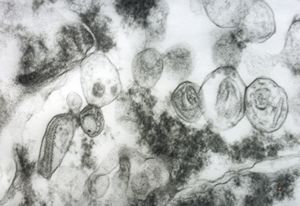

F, 24y. | molluscum contagiosum … virions

F, 24y. | molluscum contagiosum

F, 24y. | molluscum contagiosum

F, 7y. | molluscum contagiosum … virions

F, 7y. | molluscum contagiosum … virions

F, 24y. | molluscum contagiosum … virions